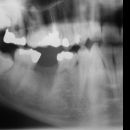

Tyto fotky, RTG snímky a OPG nám poskytl pan. MUDr. J. Novák.